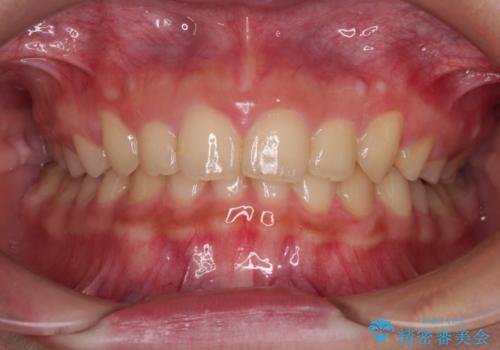

正面や横からの写真ではきれいに治っており、患者様は大変満足のいく仕上がりとなりましたが、深い咬み合わせの改善は不十分で、奥歯の咬み合わせも改善させることができませんでした。

インビザラインは、咬合力の強い方ですと、奥歯が歯肉内にめり込んでしまうため、前歯が強く接触してしまうことがあります。

こちらの方は、奥歯はしっかりと噛んだのですが、歯肉にめり込んでしまったことで、歯肉が腫れやすくなってしまいました。